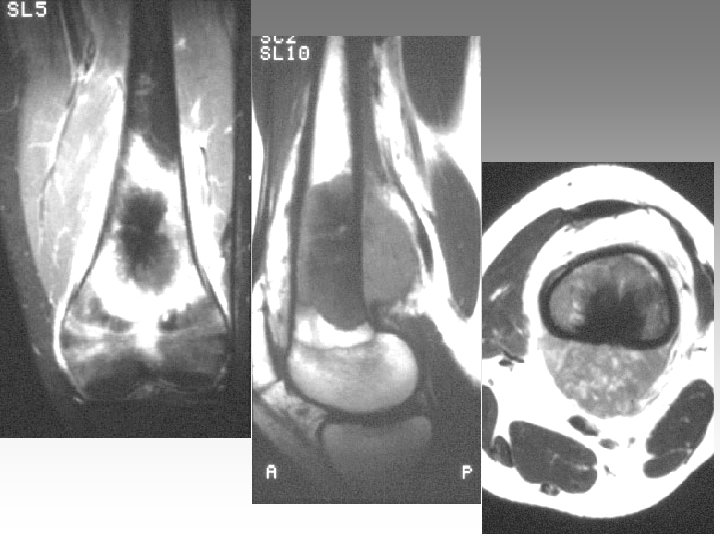

Hanche, T. , fract. fatigue Tendinites bursites, radic. Genou douloureux non traumatique Sémiologie Ponction +++ mécanique inflammatoire Rx inflammation Rx N Rx a. N < 40 ans interligne pincé Arthrose FT - FP contexte +++ > 40 ans Biologie, BS, Rx, IRM, écho interligne normal IRM AND, FF Paget, HOV ONA, OAN OAPH Ostéochond. infection IRM Arthroscopie Scinti. Os. LC Ménisque Coagul. PR, RP, Still, LED, SA…. Goutte, CCA AND ONA Ostéochondrite Pyogène, BK, Gono. , autres Hydarthrose X? Ostéochondromatose Synonite VN, T. , coag.

Genou douloureux non traumatique Sémiologie Ponction +++ mécanique inflammatoire Rx inflammation Rx N Rx a. N < 40 ans interligne pincé Arthrose FT - FP contexte +++ > 40 ans Biologie, BS, Rx, IRM, écho interligne normal IRM AND, FF Paget, HOV ONA, OAN OAPH Ostéochond. infection IRM Arthroscopie Scinti. Os. LC Ménisque Coagul. PR, RP, Still, LED, SA…. Goutte, CCA AND ONA Ostéochondrite Pyogène, BK, Gono. , autres Hydarthrose X? Ostéochondromatose Synonite VN, T. , coag.

Genou douloureux non traumatique Sémiologie Ponction +++ mécanique inflammatoire Rx inflammation Rx N Rx a. N < 40 ans interligne pincé Arthrose FT - FP contexte +++ > 40 ans interligne normal IRM AND, FF Paget, HOV ONA, OAN OAPH infection Biologie, BS, Rx, IRM, écho IRM Arthroscopie Scinti. Os. LC Ménisque Coagul. PR, RP, Still, LED, SA…. Goutte, CCA AND ONA Banal, BK, Gono. , autres Hydarthrose X? Ostéochondromatose Synonite VN, T. osseuse